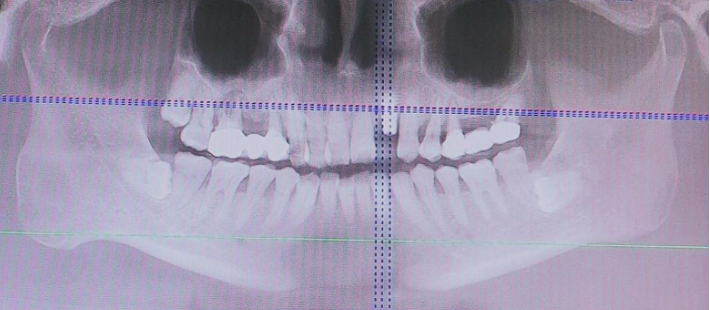

术前CBCT

21颊侧牙槽骨吸收至根尖,腭侧牙槽骨吸收至根尖1/3,根周可见低密度影。牙槽嵴宽度6.41mm。

局部反合、患牙长期牙周病变,骨质缺损,但软组织无明显缺失,为II类拔牙窝形态。

22冠状位CBCT情况

唇舌牙槽嵴宽度6.41mm,垂直骨缺失1/2,软组织无垂直向缺失。

术前术后CBCT对比

术后即刻与术后4.5个月CBCT对比

术前术后对比